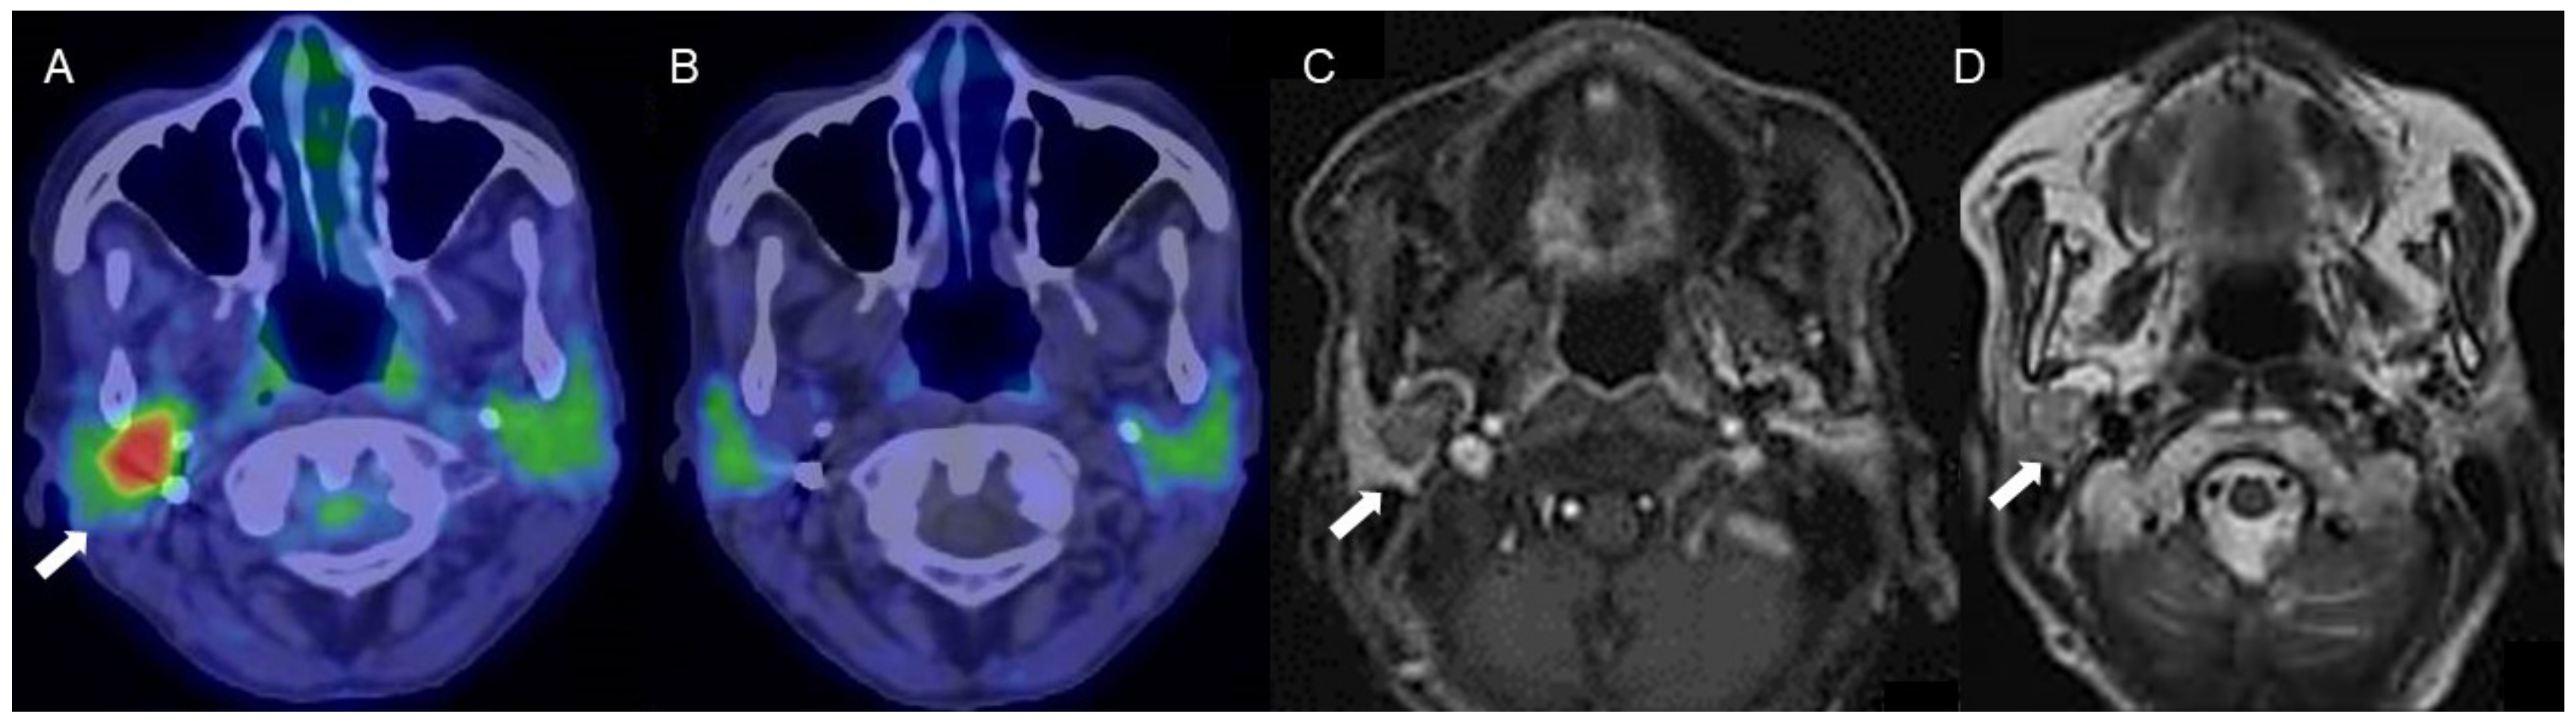

Figure 3.

A woman in her 70s with a tumor of the right parotid gland, highly suspected to be pleomorphic adenoma (arrows). (A) Fused FDG-PET/CT image (axial view), (B) fused 4DST PET/CT image (axial view), (C) Gd-enhanced MRI (axial view), and (D) T2WI MRI image (axial view). On T2WI, a well-circumscribed intraparotid mass of intermediate-to-high signal and a low-signal rim is seen, with heterogeneous nodular enhancement, characteristic of pleomorphic adenoma []. The tumor shows increased FDG uptake (SUVmax: 5.2) but no 4DST uptake.